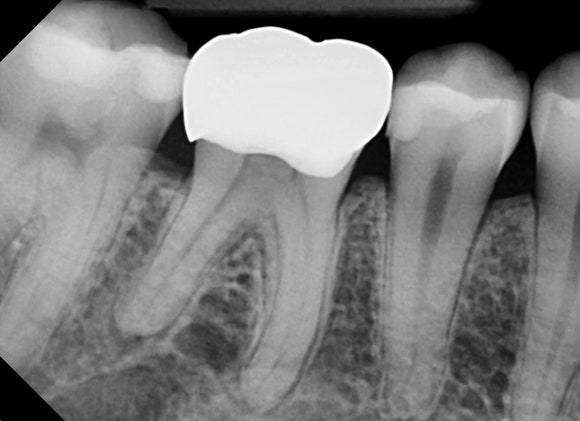

검사결과

오른쪽 아래의 크라운을 씌운 치아에서

극심한 통증이 발생하는 것을

알 수 있었습니다.

크라운의 상태는 나쁘지 않았습니다.

이전의 충치가 깊었다고 하셨습니다.

충치가 크거나 깊어도

직접적인 신경의 노출이 없는 경우,

환자분의 젊은 나이를 고려하여

신경치료 없이 크라운으로 치료를 마무리하는

경우도 많습니다.

신경과 가깝게 위치한 치과재료가

아주 약하게 지속적으로 신경을 자극하여,

혹은

시간이 지남에 따라 치아와 재료 사이의 미세누출이 생겨

추후에 시리거나 아픈 증상이 생길 수 있습니다.